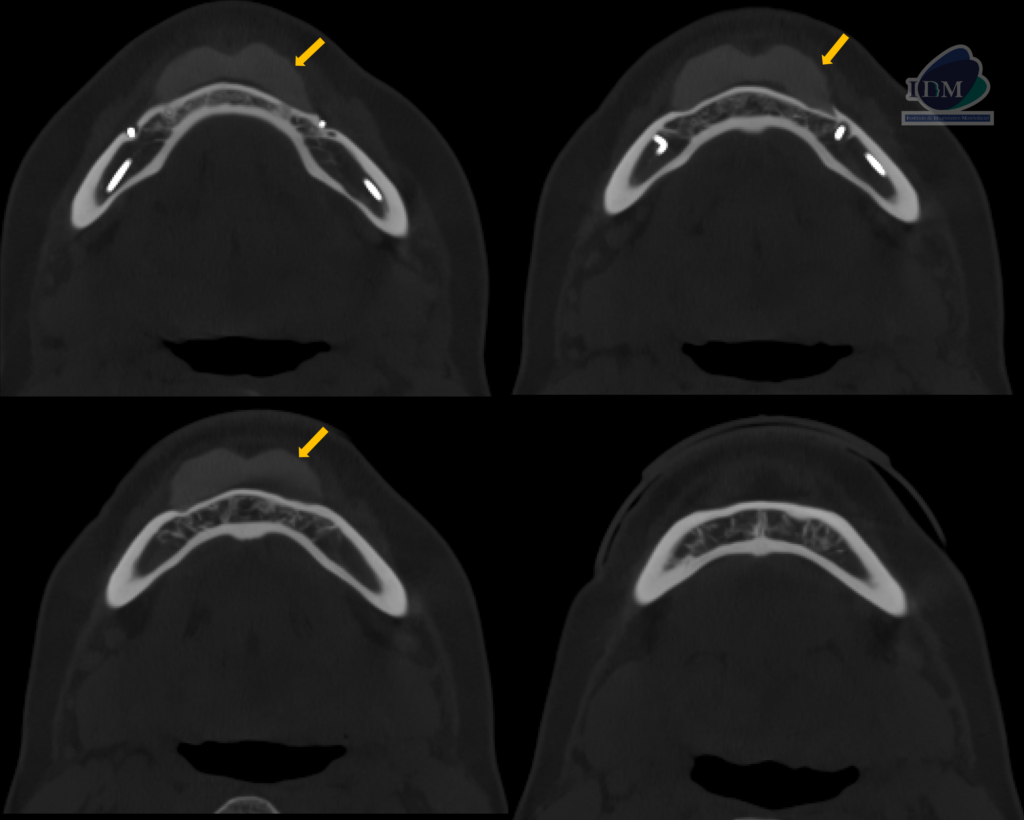

A la evaluación de la tomografía volumétrica (cone beam) en los cortes axiales (Figura 2) y transaxiales (Figura 3) se observó como hallazgo incidental la presencia de una imagen isodensa homogénea, limites definidos a nivel de la zona media de maxilar inferior, que se extendía desde pieza 33 a 43 que ocasionaba un defecto óseo en tabla vestibular de zona de piezas 33 y 43.

CORTES AXIALES